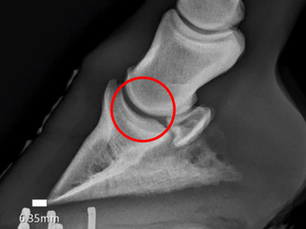

Navicular: The Current Consensus

Navicular Disease, its history, and the term’s path to obsolescence The term navicular disease has been in literature for hundreds of...